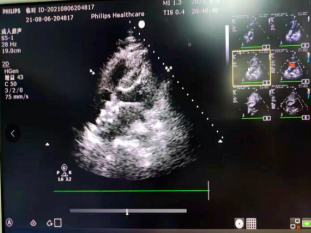

超声评估房间隔缺损有效封堵